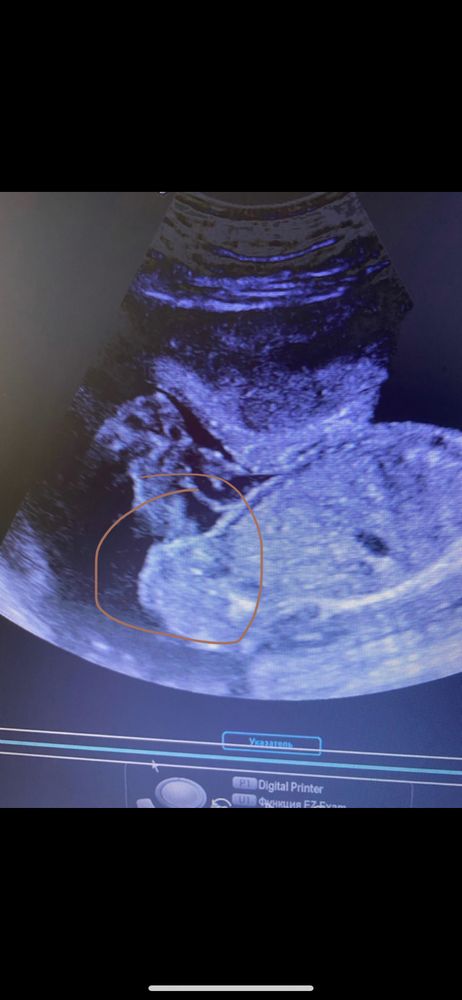

Пол в 21 неделю, скрининг

Наверное девочка)) Я вас понимаю, тоже думала что мальчик будет у меня☺️Вроде тоже девочка. Отпишитесь кто все же у вас будет, очень интересно))))

Девочка

Девочка конечно! А вам что не сказали или не верится?

Мне кажется девчонка. У мальчиков это по-другому выглядит (если мы вообще на то смотрим 😅)

Странно, что вам не сказали, тк уже и в 16 хорошо видно, а так я за девочку

Больше к девочке, как по мне...